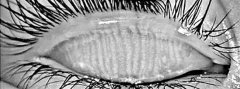

睑板腺功能障碍是一种慢性睑板腺异常,通常以睑板腺终末导管的阻塞和睑板腺分泌物质或量的改变为特征,也是引发蒸发过强型干眼症的主要原因。那么,睑板腺功能障...

睑板腺功能障碍是指睑板腺堵塞或分泌物的质量改变,引起的一些列综合征,是蒸发过强型干眼症的主要原因。睑板腺功能障碍通常分为阻塞型和非阻塞型。...

睑板腺功能障碍(meibomain gland dysfunction,MGD)在油性皮肤及年老者中十分常见,是蒸发过强型干眼症的主要原因。它可以被广...